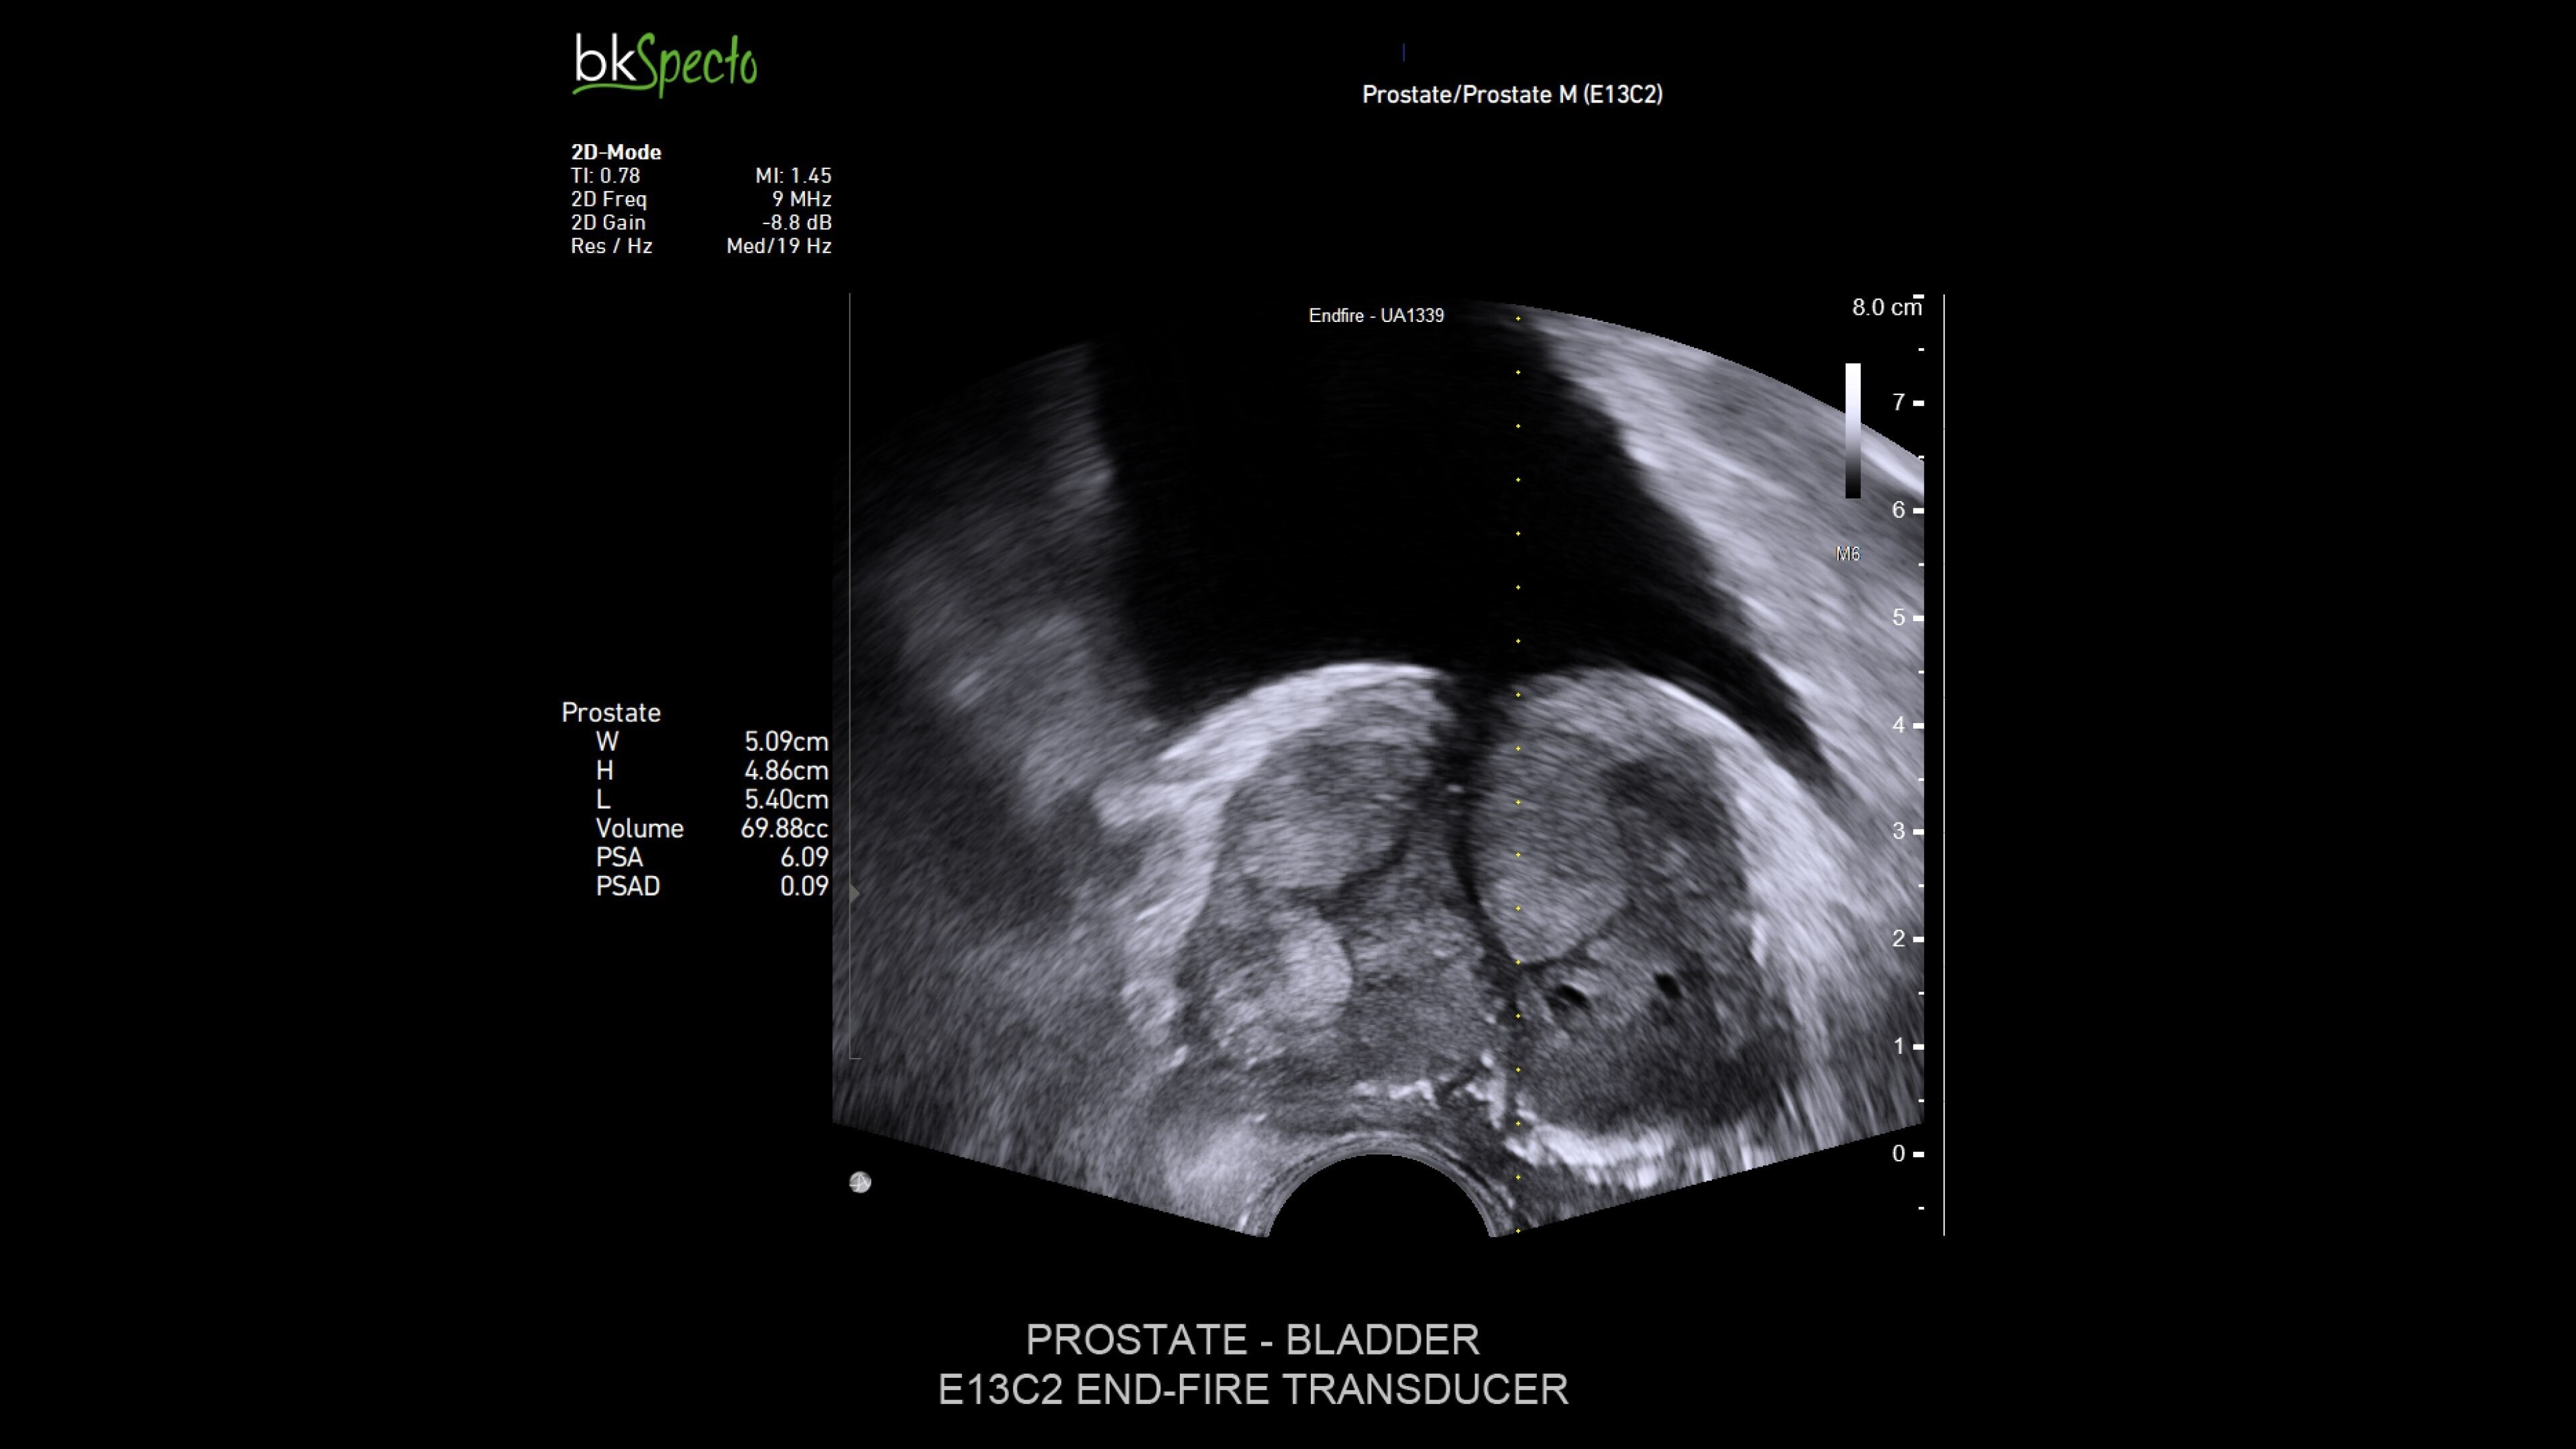

Urology

Precision ultrasound imaging for urology procedures

The bkActiv ultrasound system offers advanced imaging for urology, providing detailed visualization of the prostate, kidney, bladder, and pelvic floor (prostate imaging and biopsy, brachytherapy, cryotherapy). Its intuitive Tru-Sense™ touch interface and Smart Button™ technology allow for one-handed operation, ensuring full control during procedures. Confidently visualize and target regions for intervention with high-resolution detail and enhanced penetration when it matters most–during the procedure.1